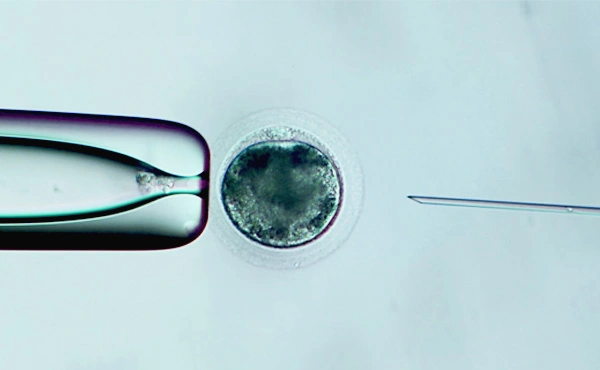

MÁS DE 20 AÑOS DE EXPERIENCIA EN EL MUNDO DE LA REPRODUCCIÓN ASISTIDA

Reproducción equina y clonación animal

En Ovohorse somos especialistas en técnicas de reproducción asistida. Nuestra amplia experiencia en el sector, gracias al primer banco de gametos humanos de Europa, Ovobank, y a nuestro grupo de clínicas Ovoclinic, nos ha llevado a desarrollar y mejorar nuestras instalaciones para ofrecer el mejor servicio. Cumpliendo siempre con estrictos protocolos de seguridad y calidad.

Confía en uno de los mejores equipos de embriólogos del mundo especializados en técnicas de reproducción asistida humana.

Equipo de embriólogos con más de 20 años de experiencia en reproducción asistida e investigación.

Centro de referencia de reproducción asistida. Instalaciones de última generación y técnicas innovadoras.

Laboratorios equipados con la última tecnología para salvaguardar el patrimonio genético del caballo.